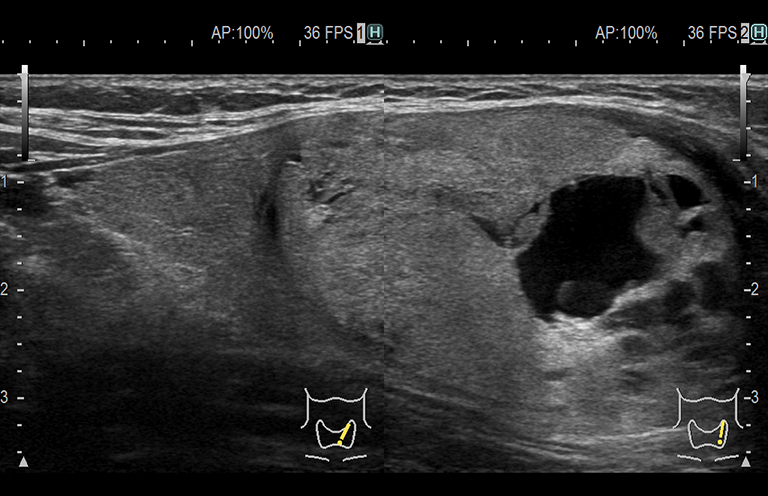

Aplicación: Mama

Función/análisis: Modo B

Comentarios: Mama

Función/análisis: Modo B(doble)